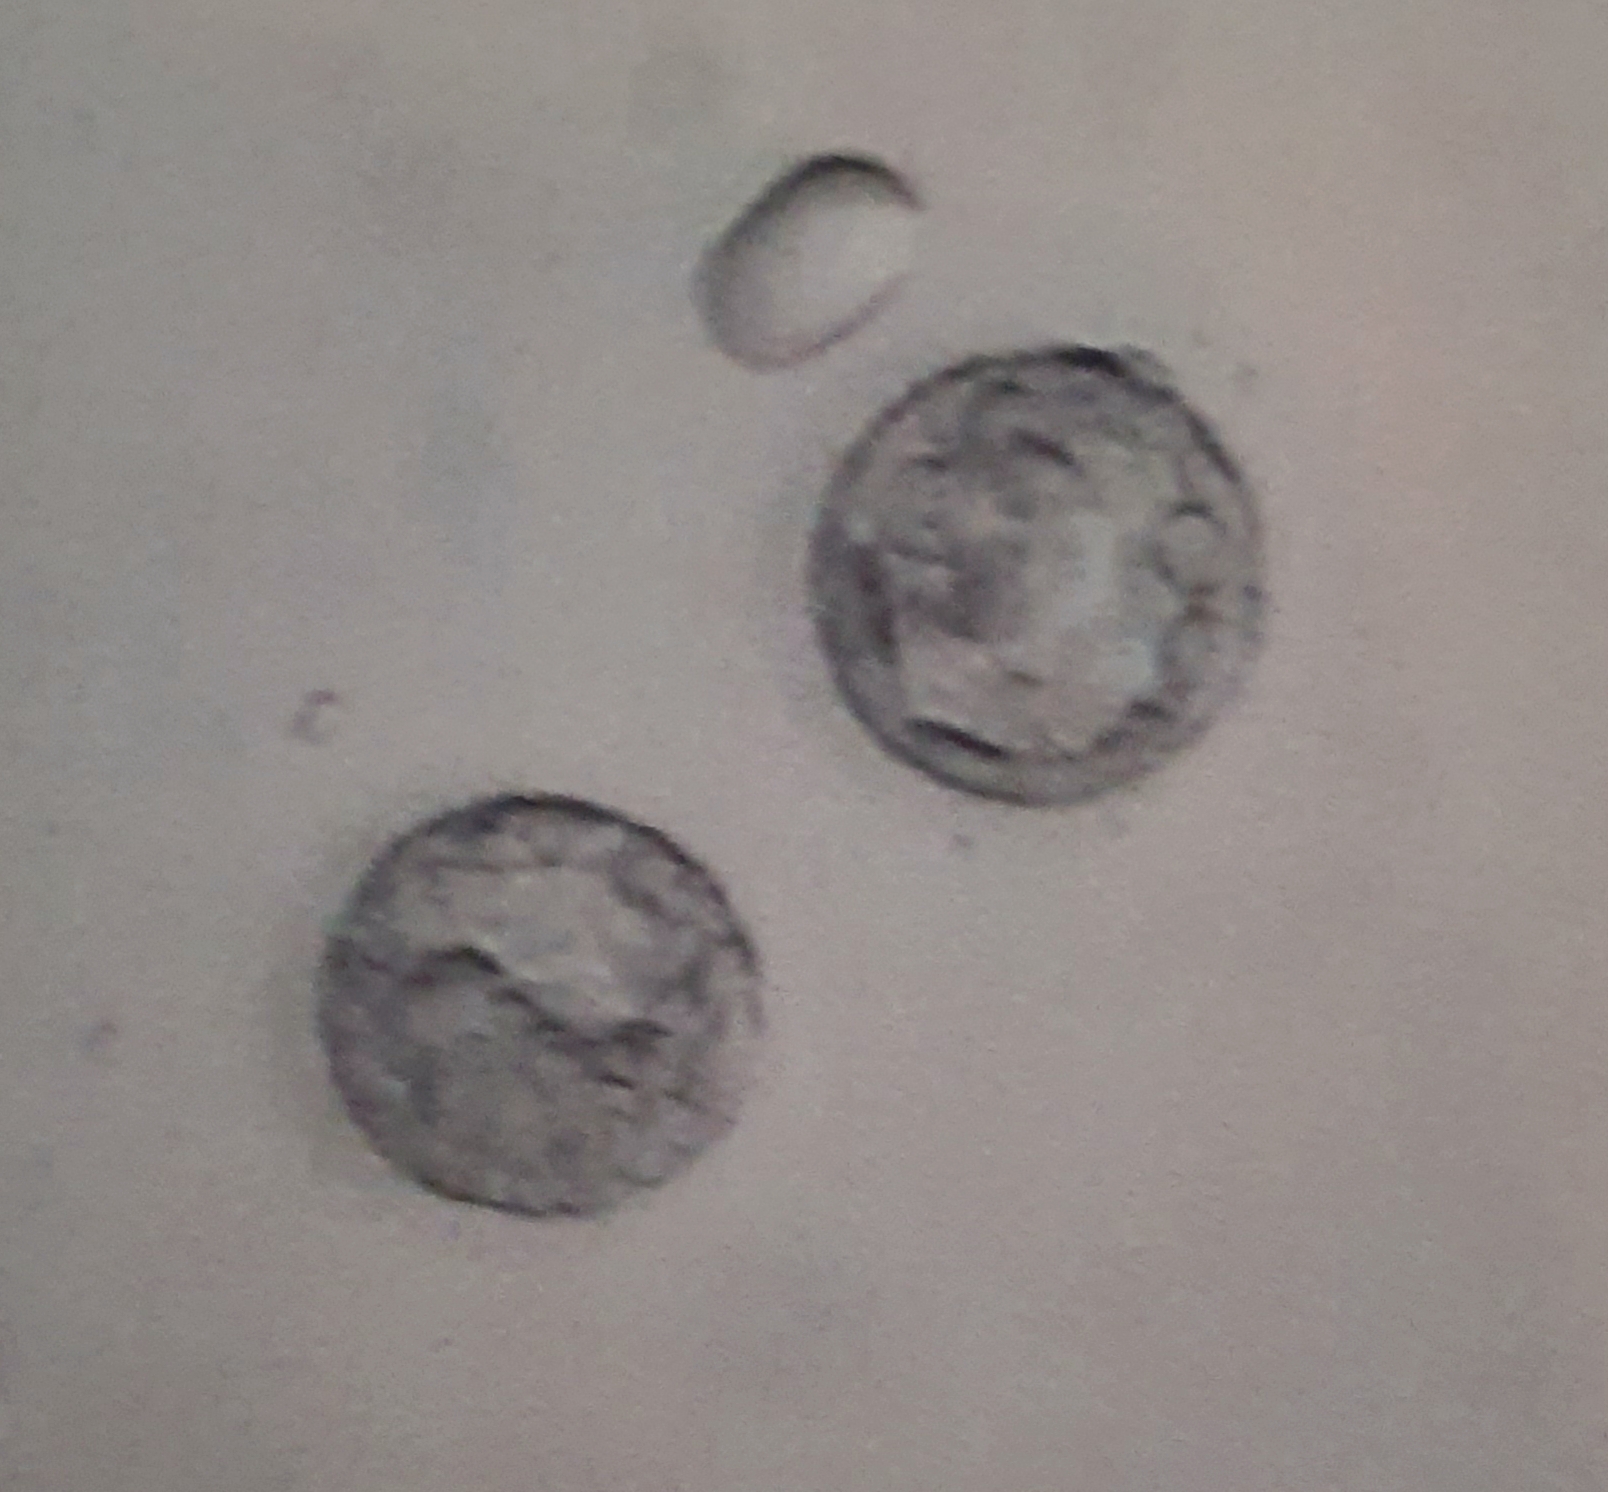

Ich versuche hier nochmal die Frage nach der Qualität meiner Blastos

mein Arzt meinte 4AA und 4AB aber für mich sehen die noch nicht so weit aus...oder?